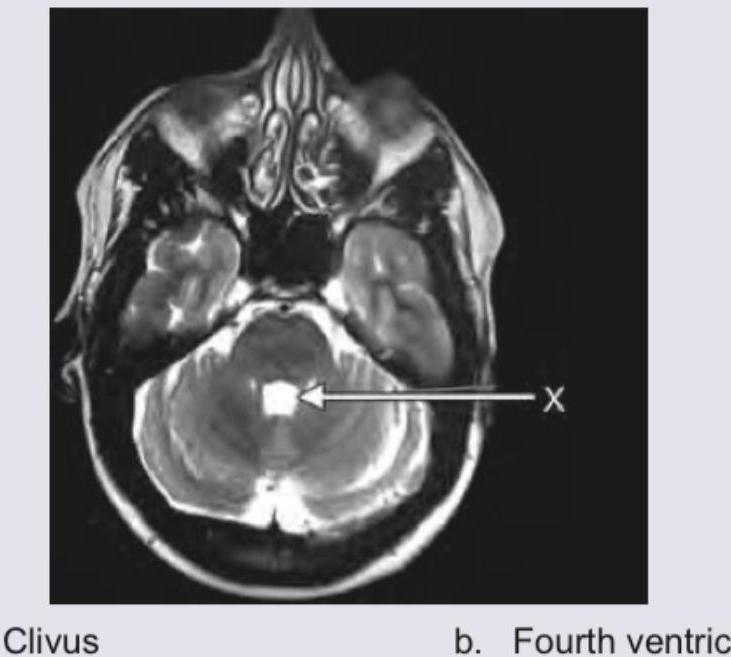

The structure marked by arrow is:

Explanation: ***Fourth ventricle*** - The arrow points to a **CSF-filled space** located between the pons/medulla anteriorly and the cerebellum posteriorly, which is characteristic of the fourth ventricle. - On this **axial T2-weighted MRI** image, CSF appears bright, clearly delineating the ventricular space. *Clivus* - The clivus is a **bony structure** forming the anterior boundary of the posterior cranial fossa, situated anterior to the brainstem. - It would appear as a **dark, cortical bone signal** on T2-weighted images and is not pointing to the fluid space as indicated. *Massa intermedia* - The massa intermedia (or interthalamic adhesion) is a band of **gray matter connecting the two thalami**, located within the third ventricle. - This structure is found much more **superiorly** in the brain, not at the level of the brainstem and cerebellum shown. *Pineal gland* - The pineal gland is a **small endocrine gland** located in the epithalamus, near the center of the brain, positioned posterior to the third ventricle. - It is located **superior to the cerebellum** and brainstem in anatomical context, not within the fourth ventricle.